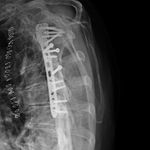

Some time in late May 2010, she presented with movement of the fracture site and was noted that the central area of healing had broken down and was thought that she had a deep infection. She was taken back to theater in mid June 2010 when operation showed that there was no pus. Multiple samples of the fracture site were taken and an external fixator applied with compression of the fragments. Following that, the cultures taken from the wounds showed no growth and no organisms and a biopsy showed no sign of any malignancy or abnormal cells. The fixator became loose and eventually had to be removed. This was done in July 2010 and she was discovered to be going onto a hypertrophic nonunion. Low dose ultrasound treatment of the fracture site was tried to help stimulate healing over the course of a few months but the non union persisted.